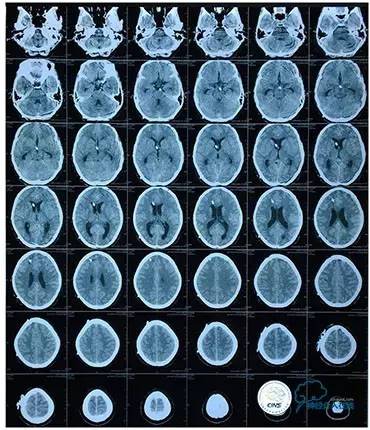

2016-5-19 MRI

2016-05-20 MRV

磁共振黑血系列